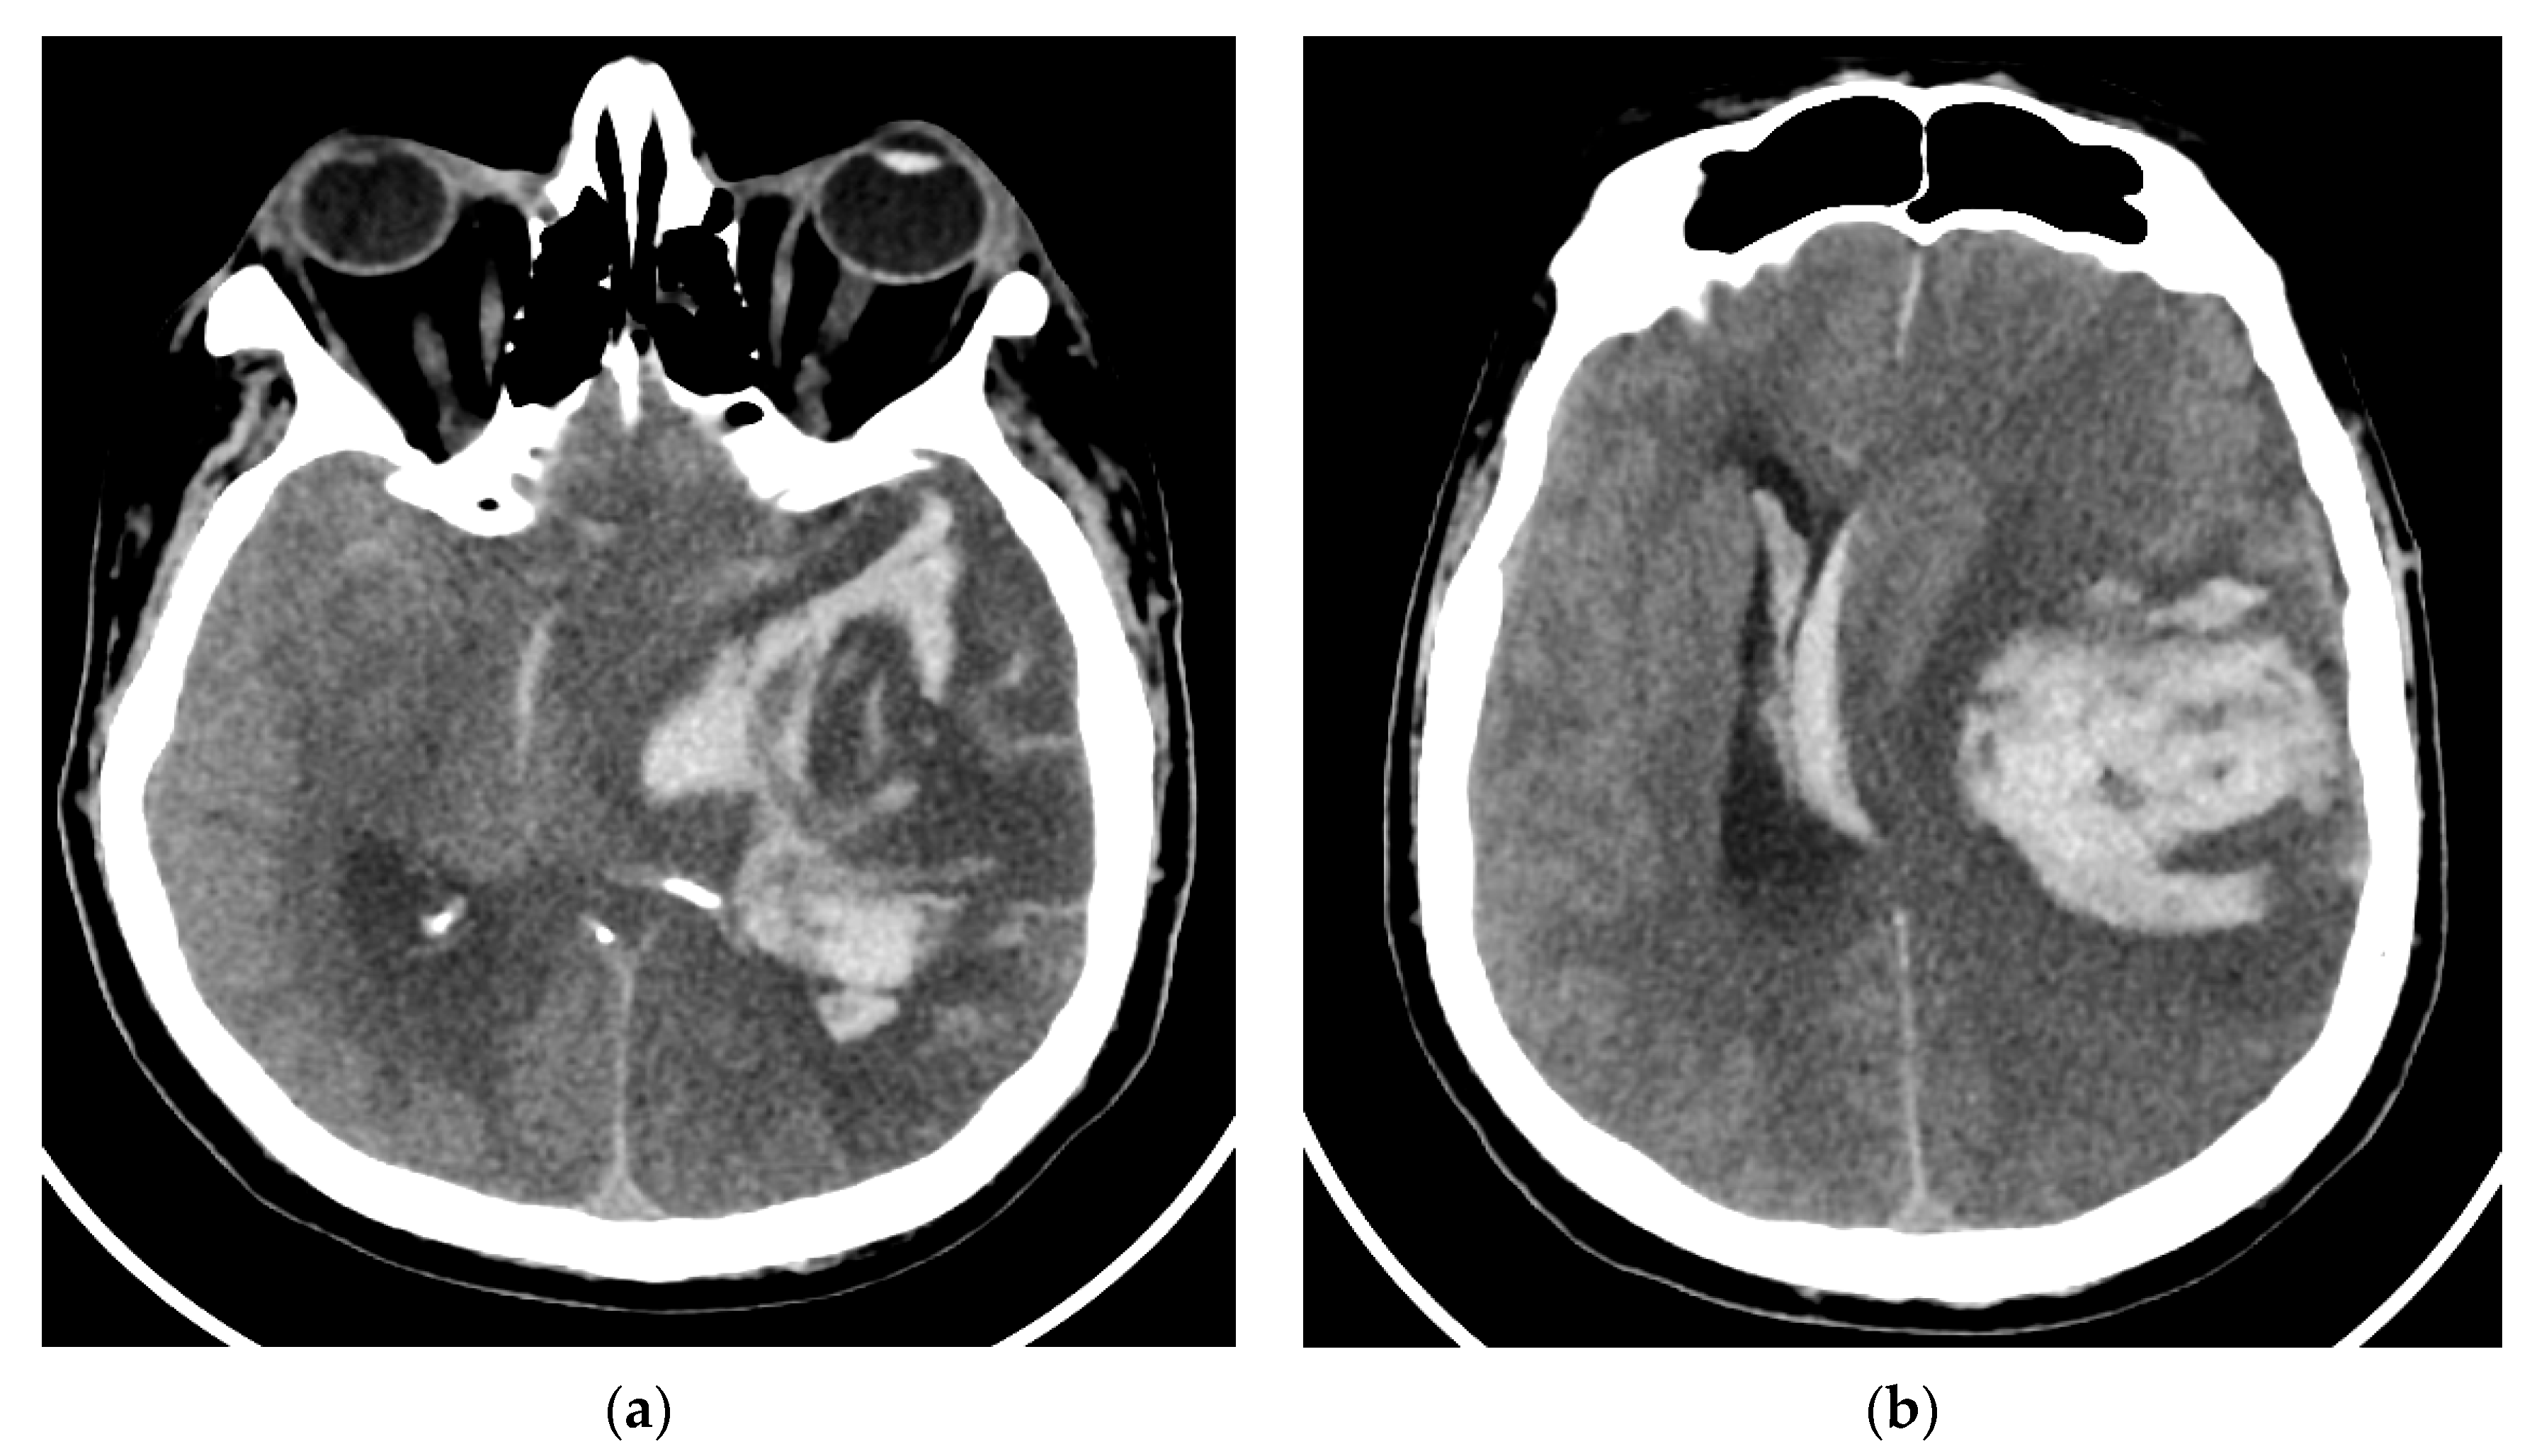

The patient returned after one month to the emergency department with right hemiparesis, mixed aphasia, incomplete left ophthalmoplegia, severe headache, and agitation, without fever. He was tested again for SARS-CoV-2 with nasal polymerase chain reaction (RT-PCR) and was found to be positive. His vitals were stable and non-contrast brain CT showed left capsulo-lenticular and temporal hypodensities. MRI brain images with and without contrast showed aspects in T2, Flair, and DWI hypersignal without contrast capture of the left temporal cortex, respectively, the hippocampal and ipsilateral parahippocampal region. An MRI brain scan also revealed multiple images in hypersignal T2, Flair, and DWI with dimensions of 2–10 mm located juxtacortically and deeply periventricular fronto-temporo-parietal bilateral. The appearance was suggestive of encephalitis (Figure 2).

Figure 2. MRI brain images with contrast showed aspects of T2 axial Flair hypersignal in the left temporal lobe (a,b), respectively, in the hippocampal and parahippocampal region (c). The lesion is hyperintense on the DWI axial image (d). MRI: magnetic resonance imaging; Flair: fluid attenuated inversion recovery; DWI: diffusion weighted imaging.